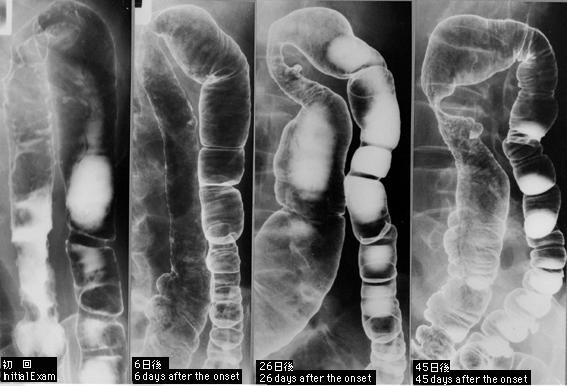

A case of stricture type ischemic colitis followed by 4 barium enema examinations over a 50-day period.

Tokyo Pref., Cooperative study between National Cancer Center and Kyushu Cancer Center

female

60-64

Inflammatory or ulcerative disease / lesions/Ischemic colitis

Large intestine(Colon)/More than one of the above

X-ray